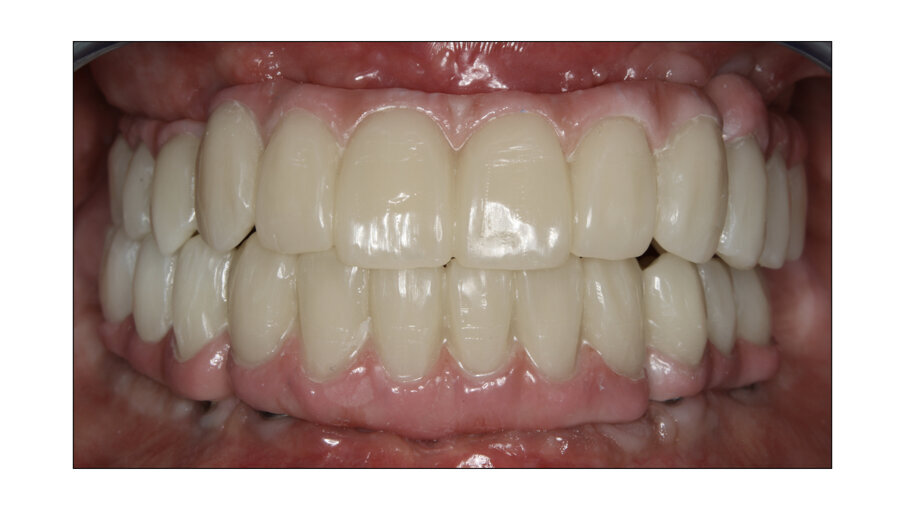

In this case, a patient presented with extremely atrophic bone in the mandible, with four short implants placed between the dental nerve foramen (Figs, 10a, 10b). After some time, patients wearing this kind of restoration with prefabricated teeth, their muscle activity increase considerably, which very often leads to fracture or debonding of the prefabricated teeth (Fig. 12). A combination of a rigid metal structure over the telescopic bar and a thimble structure made of PEEK (Fig. 13, 14) works as base for the final restorations. These were milled out of a BRILLIANT Crios disc either as single tooth units or bridges and cemented on the thimble structure (Figs. 15-17). Using BRILLIANT Crios instead of prefabricated teeth, we can increase the strength of the restoration, have good aesthetics and keep the weight low for this kind of prosthesis.

Fig. 18: Final case in the mouth of the patient. Wearing a complete denture on top and tele-copic BRILLIANT Crios on the lower jaw.